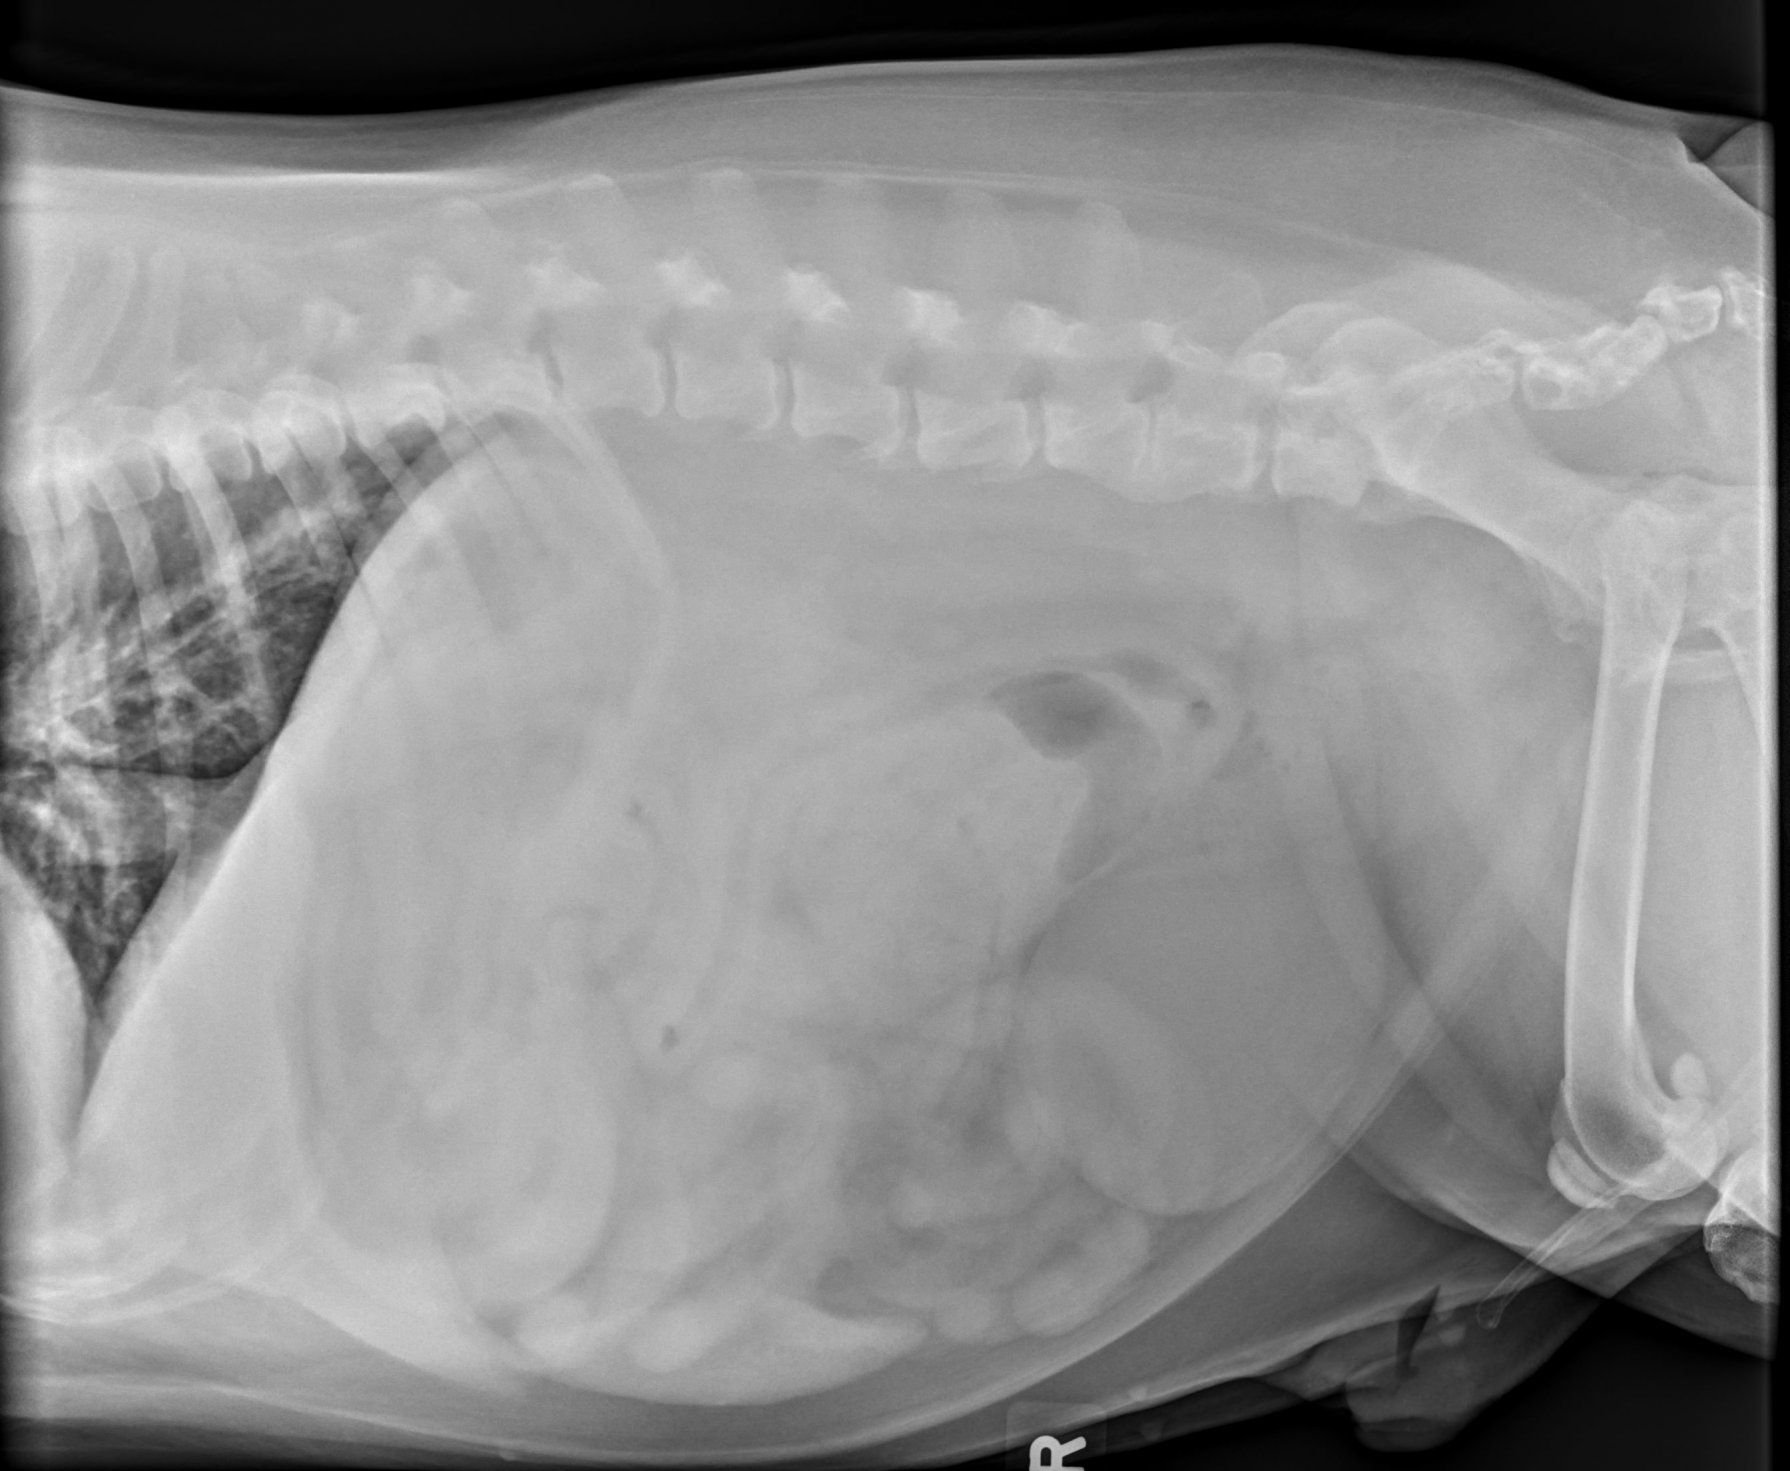

I wanted to show you guys the second set of xrays done on Tyson after the first sock came out. They are different angels, obvs. but you tell me if you see anything that looks odd. BC I know I'm not crazy, and I've had 5 other ppl tell me they see the same thing. And these were confirmed by a "radiologist" that there was nothing foreign present. Take a look for yourself. (PS the more obvs. black is gas) Look at his stomach.

Now, I was told that since this "black area" couldn't be seen in both images, it was nothing. And I should have photographed the 2nd sock when it came out, bc I swear to you, it looked just like it does in photo #2.

So, the black spot in second pic is'normal' ??